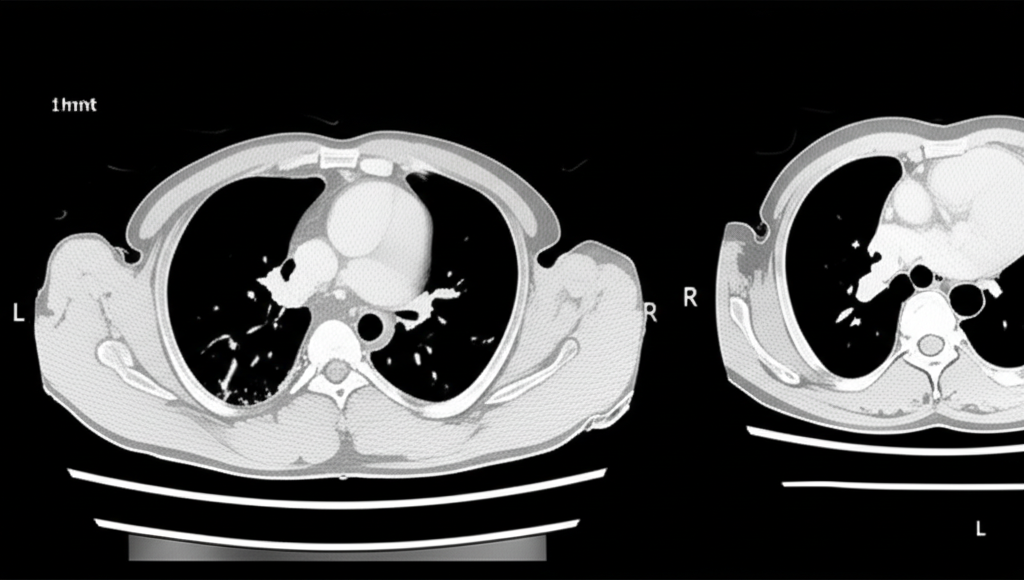

폐 CT는 폐 질환 진단에 매우 중요한 역할을 하는 영상 검사입니다. 흉부 X선 검사보다 훨씬 더 자세한 정보를 제공하여 폐암, 폐렴, 만성 폐쇄성 폐질환(COPD) 등 다양한 질환을 조기에 발견하고 정확하게 진단하는 데 도움을 줍니다. 건강 검진 시 폐 CT 검사를 고려하는 것은 건강한 삶을 유지하는 데 매우 현명한 선택입니다.

폐 CT로 알 수 있는 것은 폐암뿐만 아니라 폐렴, 결핵, 기관지확장증, 간질성 폐질환 등 다양한 폐 질환을 진단하는 데 유용합니다. 이러한 질환들은 호흡 곤란, 기침, 가래 등의 증상을 유발할 수 있으며, 심한 경우 생명을 위협할 수도 있습니다. 폐 CT 검사를 통해 이러한 질환들을 조기에 발견하고 적절한 치료를 받으면 질병의 진행을 늦추고 합병증을 예방할 수 있습니다.

폐 CT는 COPD 환자의 폐기종 정도, 기관지 확장 여부, 폐렴 발생 여부 등을 평가하는 데 사용됩니다. 이를 통해 COPD의 진행 정도를 파악하고, 적절한 치료 계획을 수립하여 환자의 삶의 질을 향상시킬 수 있습니다.